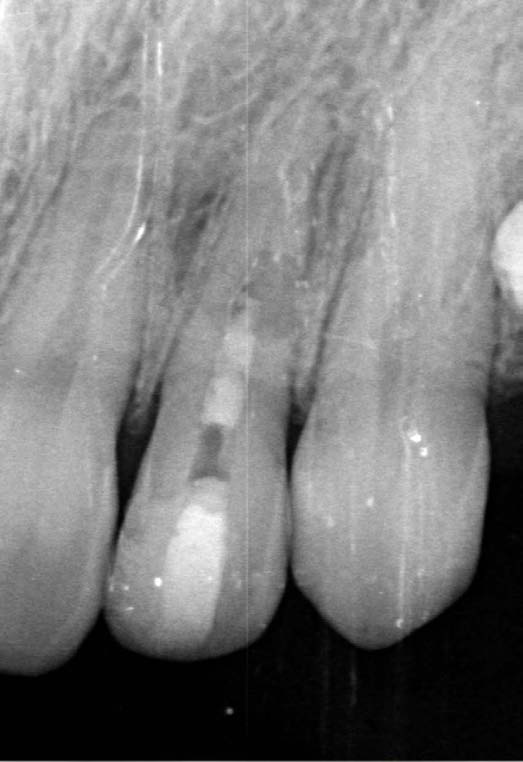

The X-ray snapshots showed signs of internal resorption in tooth 2.2.

The CBCT revealed intraroot perforating resorption on the vestibular root surface. In addition, a possible cause of resorption was identified as Oehlers' Type I invagination (1957), which was based on the radiological findings. According to the classification, Type I invagination is covered with enamel and is located within the coronal part, extending no further than the enamel-dentin junction. The authors believe that the infected invagination zone with subsequent creeping infection of the root pulp brought about the resorption. The response to the cold stimulus was very insignificant, especially in comparison with tooth 12. This made it clear that an irreversible destructive process is going on in the damaged tooth. Since the patient was planning orthodontic treatment and the resorption process could grow worse, it was decided to conduct endodontic treatment.

The radiographic findings were very similar to external resorption, but some moments were not typical of it.

In favor of external resorption was the shape of the defect, with the wider defect facing the bone, the shape of the defect was not rounded, which would be characteristic of internal resorption.

Also, there were signs in favor of internal resorption. The defect was below the cervical part, which is not typical of external cervical resorption. The response to cold stimuli reduced, which is not characteristic of external resorption, as it affects the pulp only in the last stages of tooth structures decay. Furthermore, the X-ray obliteration of the root canal beyond the resorption area is not characteristic of external resorption. Visit 1: Pre-op X-ray plus anesthesia with sol. Ubisthesini 4% -1 ml, isolation with rubberdam. The access was made as close as possible to the incisal edge. When opened, at first glance the pulp chamber looked quite II.